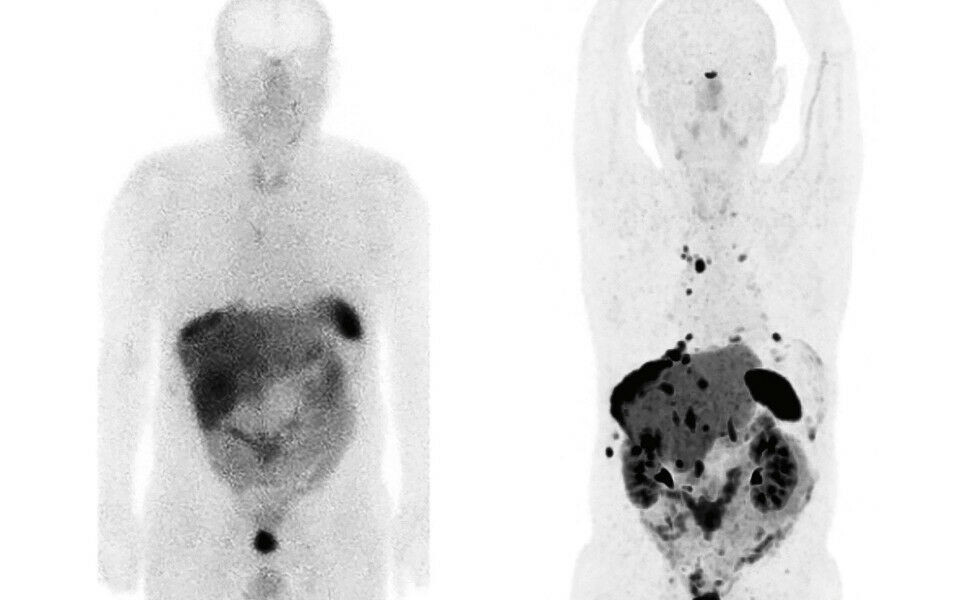

Den nye undersøkelsesmetoden er betraktelig bedre med høyere spesifikk bindingsevne til reseptorer på celleoverflaten i svulstvevet. PET-skannere er i tillegg over 10 ganger mer følsomme enn SPECT-skannere (figur 1).

Etableringen av 68Ga-DOTATOC PET/CT har vært en lang prosess. Vi har hatt nytte av å hospitere ved Senter for nukleærmedisin/PET på Haukeland Universitetssjukehus (som etablerte metoden høsten 2017), samt deltakelse på Europeisk kongress i Nukleærmedisin (Düsseldorf, høst 2018) hvor vi så på nødvendig utstyr fra ulike leverandører. I tillegg har vi jobbet tett med leverandøren av generatoren for praktisk tilrettelegging og opplæring. De var også til stede under vår første pasientundersøkelse. Bildene vi nå fremstiller på PET/CT-skanneren er av høy kvalitet, og de kan knapt sammenlignes med bildene kjørt etter gammel metode med SPECT/CT.